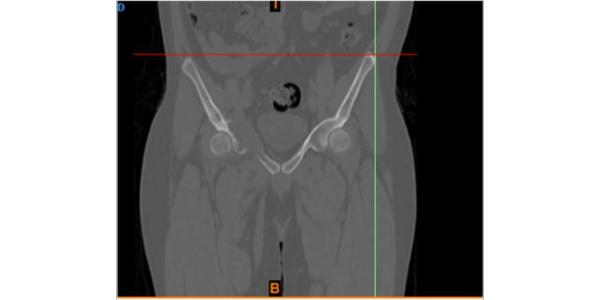

A newly married male 25 years old suffering from cancer of right pelvic bone. The difficulty in the case was the site of his cancer which was very rare, around the hip joint, which is major joint in body surrounded by vital organs.

Dr. Himanshu Rohela leading Onco Orthopedic surgeon in Mumbai, Maharashtra after studying the scan and his previous treatment records, concluded that the patient is suffering from cancer of right pelvic bone having tumor. The challenge was to save the leg thus using Patient Specific Cutting Guides and Patient Specific Hip implant. Incredible team discussed with Dr. Rohela, the designing and entire manufacturing process. It initially started with surgical planning and case simulation with the help of US FDA & CE approved Materialise Mimics software by superimposing CT & MRI DICOM data & Anatomical Model. As Anatomical model maintained 1:1 ratio with the anatomy, hence showed excellent detailing of the defect, the model was also used to design jigs & implant on actual bone, which further helped the pre surgical planning. Once the planning was finalized, the surgery was accompanied with not only Customized Implant but also Cutting guides & Jigs. Read more